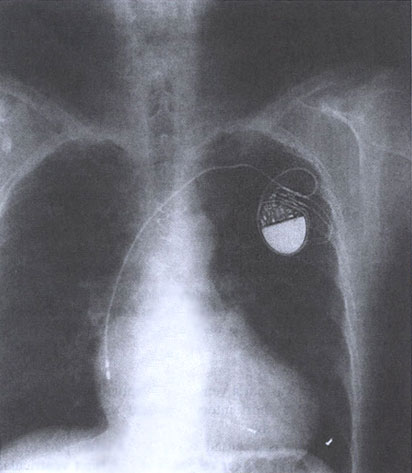

Figure 16 p Chest x-ray showing a single lead in the heart. Note the bipolar electrodes in the atrium and the single electrode in the ventricle. This pacemaker system is capable of VDD pacing. Therefore, it senses atrial depolarizations and can pace or sense in the ventricle. Mitrani,R.D. and others,Cardiac Pacemakers,Hurst's The Heart,10th edition,Vol.1,pp.963-992 |